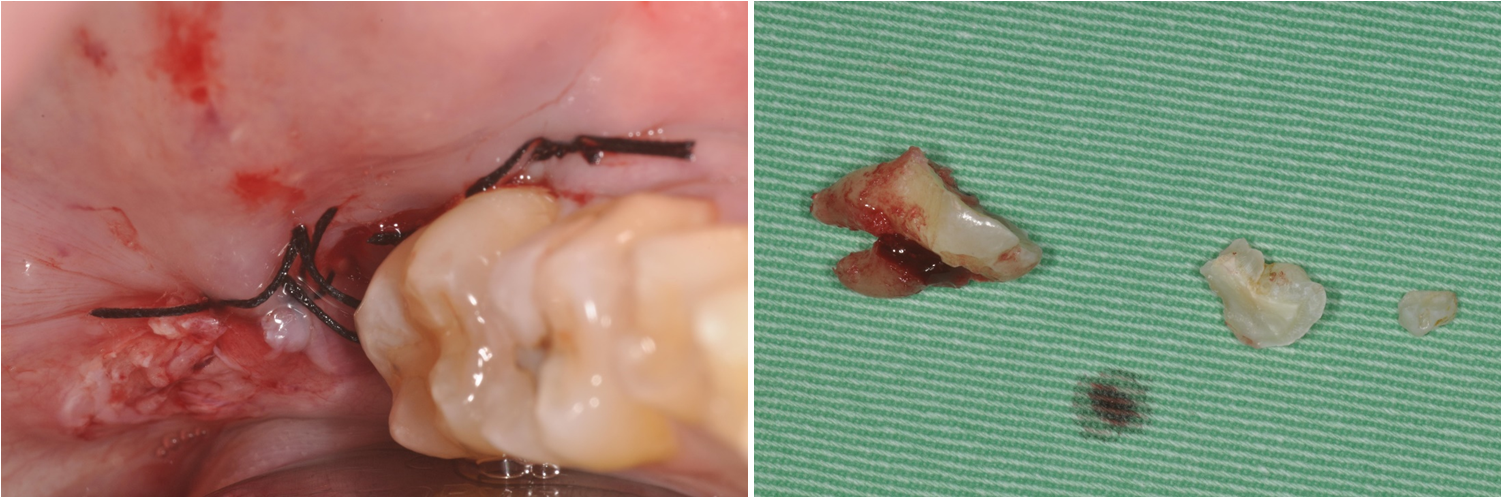

以骨膠原修復,並縫合之